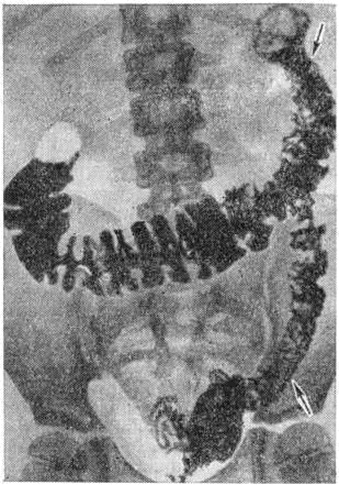

Язвенные дефекты (смотри полный свод знаний Язва), имеющие при Крона болезнь характер узких трещин, проникают глубоко в стенку кишки, достигая иногда субсерозного слоя. С поверхности язвы покрыты тонким некротическим слоем, под которым располагается грануляционная ткань. Деструктивно-язвенные изменения и воспаление обусловливают возникновение осложнений. Типичным осложнением являются спайки, иногда с образованием конгломератов петель тонкой кишки. Часто возникают разнообразные внутренние (обычно межкишечные) и наружные свищи. Перфорации в свободную брюшную полость наблюдаются редко из-за развития спаечного серозита. Воспалительно-некротическое поражение того или иного участка желудочно-кишечные тракта при Крона болезнь сопровождается обычно такими изменениями, как расширение лимфатических, сосудов и лимфангиит (смотри полный свод знаний), перестройкой слизистой оболочки кишок с деформацией крипт и распространённым повреждением микроворсинок, развитием невромоподобных образований. Клиника и течение. Болезнь не только по локализации, но и по течению может выражаться в разнообразных формах. Острая форма сходна с энтерогенными флегмонами желудочно-кишечные тракта, описанными М. Г. Черепашинцем (1956) и М. Д. Моисеенко (1958). Заболевание протекает обычно с умеренными болевыми ощущениями в различных отделах брюшной полости, часто кровавыми поносами, субфебрильной температурой, умеренным лейкоцитозом, повышением РОЭ. При переходе острой формы в хроническую (около 10%) или при первично-хроническом медленно прогрессирующем процессе, который иногда длится многие годы и захватывает почти всю толстую кишку или значительную часть тонкой, в брюшной полости образуются плотные инфильтраты. Некоторые формы хронический Крона болезнь получили название гранулематозного эзофагита-гастрита, илеита-колита, илео-колита. В отдельных случаях хронический трещины заднего прохода и параректальных свищей могут являться проявлением Крона болезнь Заболевание вначале может протекать бессимптомно. При длительном течении (годы, десятилетия) инфильтрация стенок может распространяться по протяжению всей тонкой или толстой кишки. Раньше или позже появляются клинические, проявления и различные местные осложнения и общие изменения. Местные осложнения — перфорация кишки в брюшную полость, в результате чего может развиться перитонит (смотри полный свод знаний), перфорация в соседний орган — внутренний свищ (смотри полный свод знаний Кишечные свищи), внутрикишечное кровотечение (смотри полный свод знаний Желудочно-кишечное кровотечение), спаечные процессы (смотри полный свод знаний Спаечная болезнь), паралитическая дилатация кишки или образование инфильтратов, напоминающих туберкулёз или паразитарные (эхинококк, актиномикоз) процессы, а также злокачественные новообразования. Общие изменения имеют интоксикационно-аллергическую природу. К ним относятся дистрофические процессы во внутренних паренхиматозных органах, изменения крови — анемия, гипопротеинемия, диспротеинемия, уменьшение количества микроэлементов в крови, высокая РОЭ и повышенная свёртываемость крови, неспецифические ревматоидного типа поражения суставов конечностей и позвоночника, поражения глаз в виде кератитов, язв роговицы, иритов, иридоциклитов, эписклеритов, гнойные и гранулематозные процессы в коже — экзема, пиодермия, фурункулёз, узловая эритема и другие Диагноз затруднителен. При остром терминальном илеите нередко ставят диагноз — острый аппендицит (смотри полный свод знаний) и оперируют больного. При хронический течении заболевания диагноз с некоторой долей вероятности может быть поставлен на основании описанных симптомов, данных рентгенологическое исследования, результатов эндоскопии. Ведущим рентгенологическое симптомом Крона болезнь является сужение поражённого участка кишки (рисунок 1). При резком сужении поражённый отдел кишки приобретает вид «шнура» или «верёвочки». Если такому изменению подвергаются слепая кишка и терминальная часть подвздошной, то трудно определить область илеоцекального перехода. Изменённый фрагмент кишки обычно не заполняется туго контрастной массой, особенно в период обострения болезни. Рельеф слизистой оболочки имеет полиповидный характер. При поражении Крона болезнь толстой кишки гаустры сглаживаются или исчезают. Контуры поражённого участка кишки чаще всего бывают мелкоили крупнозубчатые, нередко с характерными для Крона болезнь остроконечными спикулоподобными выступами (рисунок 2), которые являются отображением поперечно расположенных и глубоко проникающих в стенку кишки щелевидных изъязвлений. Иногда язвы, распространяясь в глубину стенки кишки, обусловливают на рентгенограммах своеобразную картину «шляпок гвоздей», располагающихся правильными рядами по контурам поражённой кожи. Важным признаком является укорочение изменённых отрезков тонкой или толстой кишки. Граница со здоровыми участками стенки кишки чаще резкая. Характерно для Крона болезнь чередование поражённых фрагментов кишки с нормальными.

Изменения слизистой оболочки рентгенологически проявляются крупноили мелкоячеистой структурой внутренней поверхности кишки, напоминающей булыжную мостовую. На фоне перестроенного рельефа слизистой оболочки могут обнаруживаться различные по величине стойкие контрастные пятна — отображение продольных и поперечных язв и эрозий. При двойном контрастировании кишки (взвесью бария и воздухом) более отчётливо определяются сужение поражённого участка кишки, неровность его контуров, псевдодивертикулярные выпячивания, ригидность стенок, резкость границ с нормальными стенками, ячеистая структура рельефа слизистой оболочки (рисунок 3). При дифференциальном диагнозе необходимо иметь в виду следующие заболевания: язвенный неспецифический колит (смотри полный свод знаний), хронический колиты другой этиологии (смотри полный свод знаний Колит), опухоли, дивертикулит, туберкулёз, актиномикоз (смотри полный свод знаний Кишечник), саркоидоз (смотри полный свод знаний), венерическая лимфогранулема (смотри полный свод знаний Лимфогранулематоз паховый). В дифференциальной диагностике Крона болезнь с язвенным колитом следует учитывать, что при язвенном колите чаще поражаются дистальные отделы толстой кишки. Псевдополипы при этом, в противоположность Крона болезнь, располагаются беспорядочно, имеют неправильную форму и нечёткие очертания. Сужение кишки развивается реже и позднее. Рубцово-стенотическая форма туберкулёза кишечника характеризуется значительным сморщиванием поражённого участка кишки, наличием выраженных спаек, увеличением брыжеечных лимфатических, узлов, бесструктурной перестройкой слизистой оболочки кишки, выраженными функциональный расстройствами соседних нормальных участков кишки. Лечение. Специфических средств для лечения Крона болезнь не найдено. При острых формах применяют антибиотики, сульфаниламиды, стероидные гормоны, что приводит к излечению или к переходу в хроническое течение. При хроническом течении Крона болезнь, помимо упомянутых препаратов, назначают симптоматическое лечение (диета и витаминотерапия, проводится борьба с анемией и другими нарушениями состава крови — гемотрансфузии, вливание белковых и солевых р-ров), введение иммунодепрессантов, восстанавливают функцию кишечника. В случае оперативного лечения, предпринятого ошибочно по поводу предполагаемого острого аппендицита, при острой форме Крона болезнь следует инфильтрировать брыжейку кишки раствором антибиотика и зашить операционную рану без аппендэктомии, т. к, удаление червеобразного отростка у таких больных нередко приводив к развитию кишечных свищей. 1